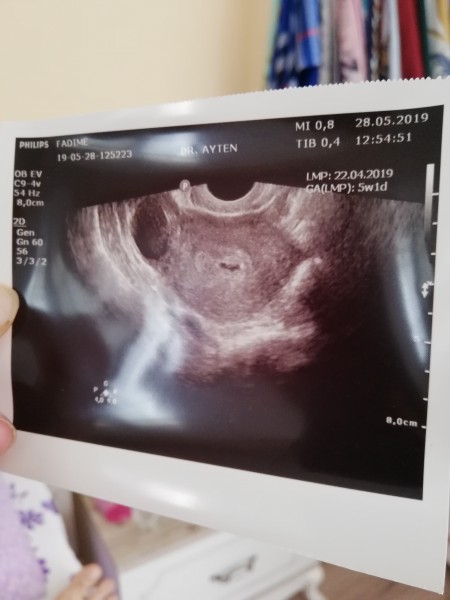

Gebelik Kesesi Ne Zaman Gorulur

Gebelik Tarihine Gore Kesenin Boyutu Nedir Saglikli Gebelik Nasil Ilerler 1numaram Com

Kese Boyutu Fotografli Hamilelik Donemi Genel

5 1 Gunluk Gebelikte Kese Var Ama Yolk Sac Gorunmedi Normal Mi Kadinlar Kulubu